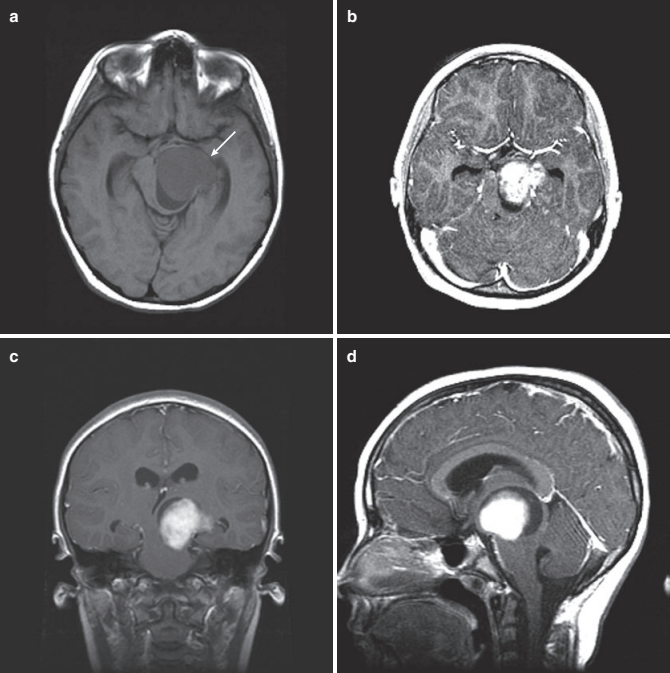

2.诊断方法: MRI是诊断这些肿瘤的金标准。由于病变与周边脑组织密度大概相同,CT可能经常检查不出来这些病变。在 T2 和 Flair MR 图像上可以更清楚地看到顶盖肿瘤,在这些图像中可以看到典型的导水管周围高信号。在大多数情况下,顶盖肿瘤是非强化病变,然而,有时候,它们也可能是背侧外生性、囊性且体积较大。如图3所示。

图3:13 岁男孩,巨大非典型顶盖胶质瘤,他患有 1 型神经纤维瘤病NF1,出现头痛和呕吐。(a) 矢状位增强 T1 MRI 显示后颅窝巨大囊性占位性病灶,位于顶盖区中心(箭头)。(b) 轴位 MRI增强MRI 显示顶盖和第四脑室的受累程度(箭头)。(c) 随后进行的后颅窝开颅手术,肿瘤囊肿的引流,并切除囊肿包膜,在这张 T1 加权增强 MRI 扫描中可见顶盖部轻微的变形(箭头)。(d) 术后 T1 加权轴位 增强MRI证实肿瘤起源于顶盖部,肿瘤切除,占位效应解除(箭头)